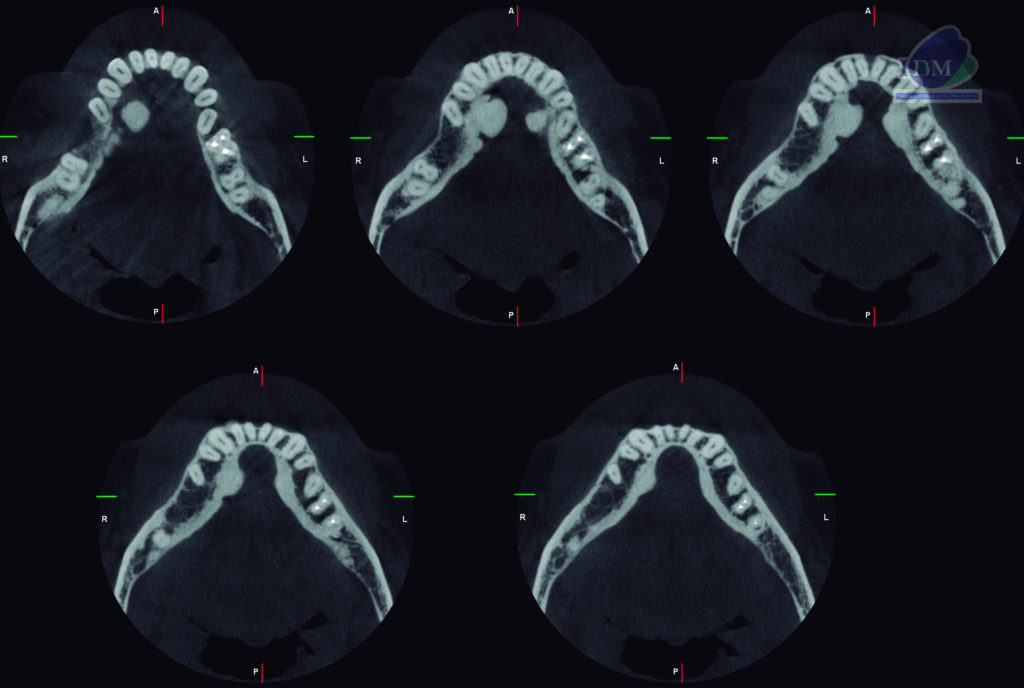

A la evaluación de la tomografía computarizada bimaxilar se observó además de los mencionado, la presencia de imágenes hiperdensas de densidad dentaria de forma irregular ubicadas por lingual, en estrecha relación con la tabla ósea y a nivel de las piezas 34-35 y 44-45 compatibles con torus mandibular.

CORTES AXIALES